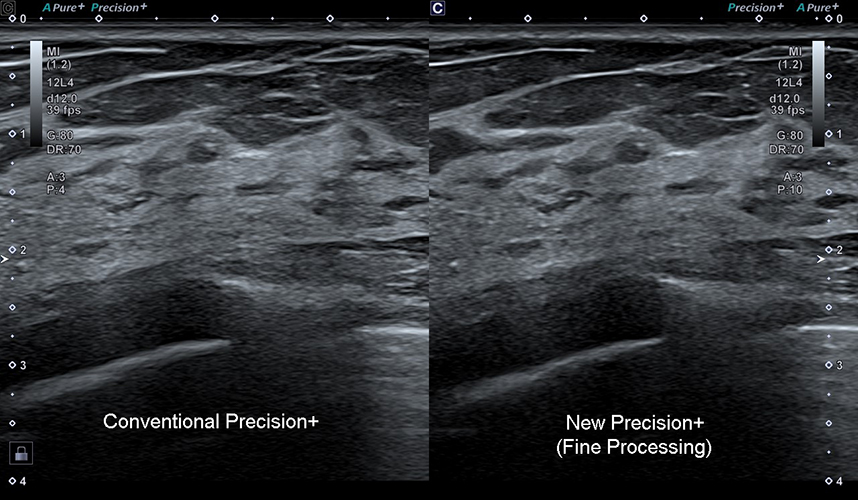

Aplio beyond sử dụng công nghệ iBeam+ và chế độ Precision+ Fine Processing giúp nâng cao chất lượng hình ảnh bằng cách giảm nhiễu, tăng độ phân giải và cải thiện độ đồng nhất hình ảnh. Điều này mang lại hình ảnh mượt mà, đường nét rõ ràng và chi tiết lâm sàng sắc nét ở nhiều ứng dụng khác nhau, từ siêu âm tổng quát đến các thủ thuật chuyên sâu.